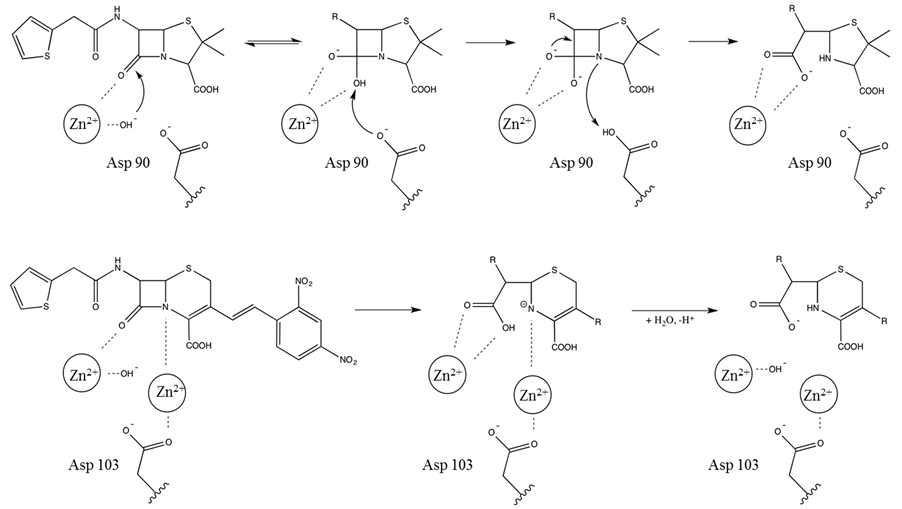

The above discussion illustrates that there is considerable variation in the active sites of MBLs from different subgroups both in terms of the composition of their first coordination spheres and the contribution of the Zn(II) ions to catalysis. Members of the B1 subgroup operate predominantly as binuclear enzymes but may still be functional in mononuclear form, albeit with reduced activity [18] [59] [60] . The B2-type MBLs only operate in mononuclear form and are inhibited if a metal ion occupies their Zn1 site [67] while the known B3-type MBLs appear to require binuclear centres [23] [24] [74] [75] . The least characterised B4-type MBLs may employ yet another mechanistic strategy where the mononuclear form is the resting, inactive form, and the catalytically relevant binuclear form is only assembled once a substrate is present [25] . Consequently, both mono- and binuclear reaction mechanisms have been proposed for MBLs [2] [8] [13] [14] [18] [19] [60] [67] [82] -[84] . Common to the various mechanistic proposals is the involvement of the metal ions in catalysis by coordinating the nucleophilic hydroxide group, which is either bridging the metal ions in binuclear centres or is coordinated to Zn2 in mononuclear MBLs (Figure 5). Despite these mechanistic variations the central and essential role of

Figure 5. Proposed reaction mechanisms for mono (upper panel) and binuclear (bottom panel) MBLs.